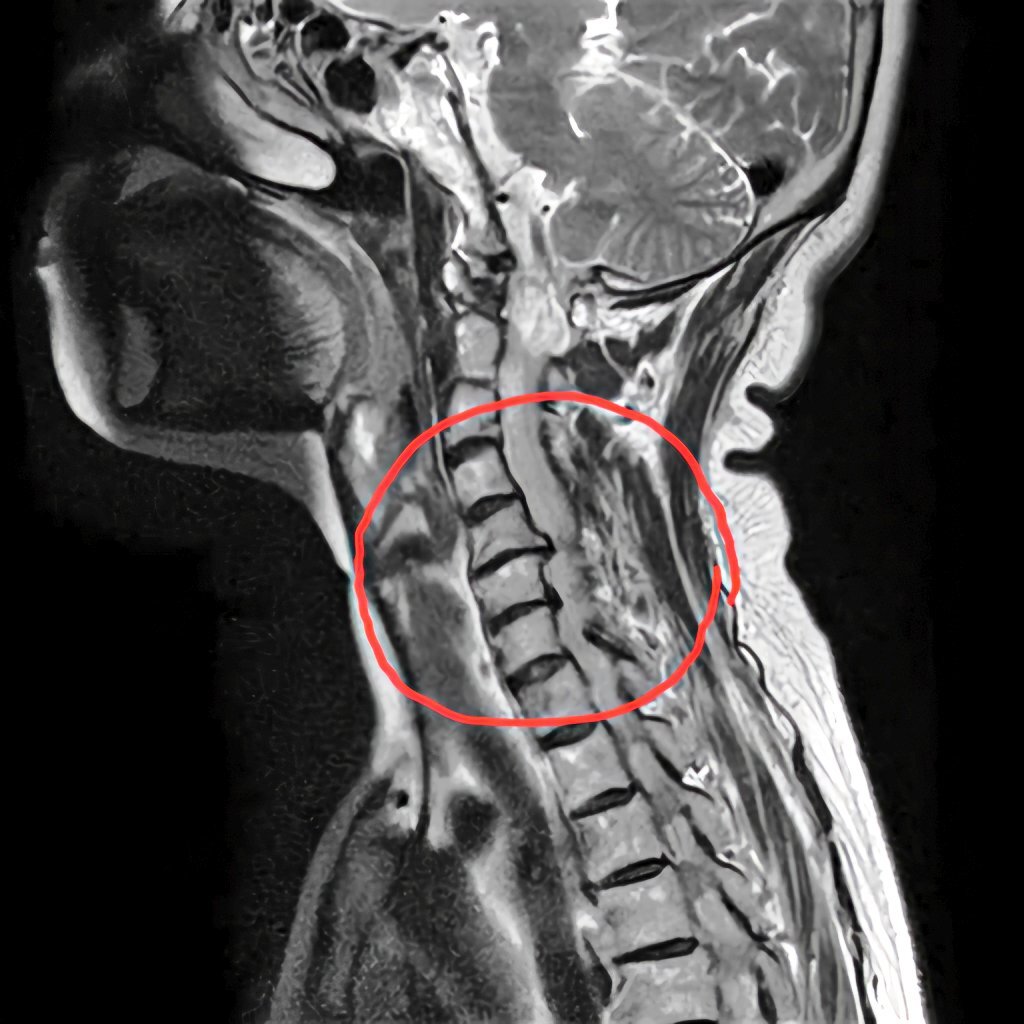

昨日診断された頸椎ヘルニアのMRI画像。縦に輪切りにされた5~6番目がずれてます。他2枚は横に輪切りにした画像。一枚は正常な頸椎で楕円になってますが、もう一枚はかなり潰された頸椎。ここが患部。なんか見てるだけで怖い。#頸椎ヘルニア #頚椎ヘルニア #椎間板ヘルニア pic.x.com/EpQGHwUqeI